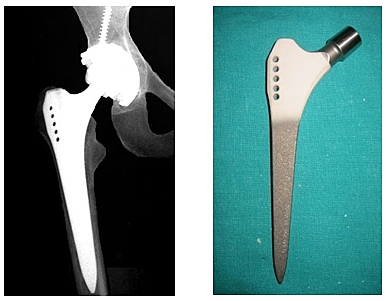

• Reemplazo de cadera, diseño endoprotesis Thompson

Reemplazo de cadera, diseño endoprotesis Thompson

Prótesis metálicas con vástagos medulares para la fijación esquelética. Desarrollados en Estados Unidos por Fred Thompson. Para fijación a presión dentro del canal medular.

• Artroplastia, con diseño endoprotesis . Moore

Artroplastia, con diseño endoprotesis . Moore

Esta prótesis presentaba una fenestración en la parte superior del vástago femoral para permitir el crecimiento óseo en su interior aumentando así su fijación ósea.